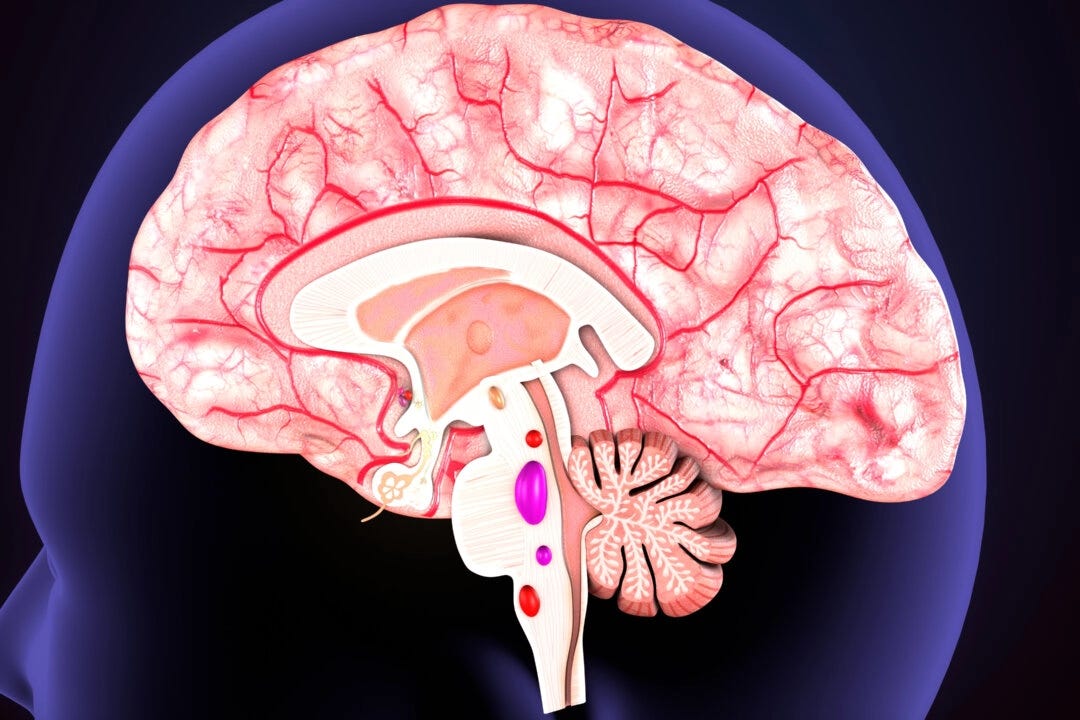

When neurons become unable to release acetylcholine, either due to age or drug effects, their contact with other neurons is reduced. The neurons and brain then start to shrink.

This has also been observed in research published by Indiana University professor Shannon Risacher, who has a doctorate in medical neuroscience. She found that people taking anticholinergic drugs have greater shrinkage of overall brain volume.

The Complex Brain